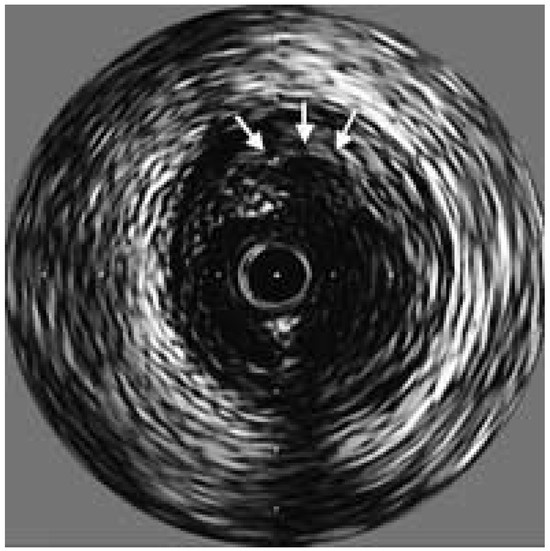

Diabetes leads to both micro- and macrovascular complications. If the major threat to type 2 diabetic patients is ischaemic heart disease, other cardiovascular complications such as heart failure, stroke and lower extremity arterial disease are also...